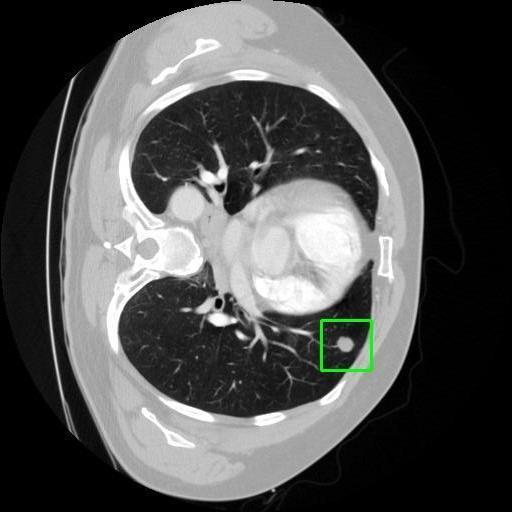

We developed an AI-based system using deep learning models for analyzing lung CT scans to detect and classify pulmonary nodules. We chose the YOLOv11 architecture for its enhanced object detection capability and adapted it specifically for medical imaging, incorporating pixel-level precision and severity classification.

Key Features: Real-time detection of nodules.

Classification into three severity levels with colored bounding boxes.

Distinguishing between similar-looking benign and malignant nodules posed classification difficulty.